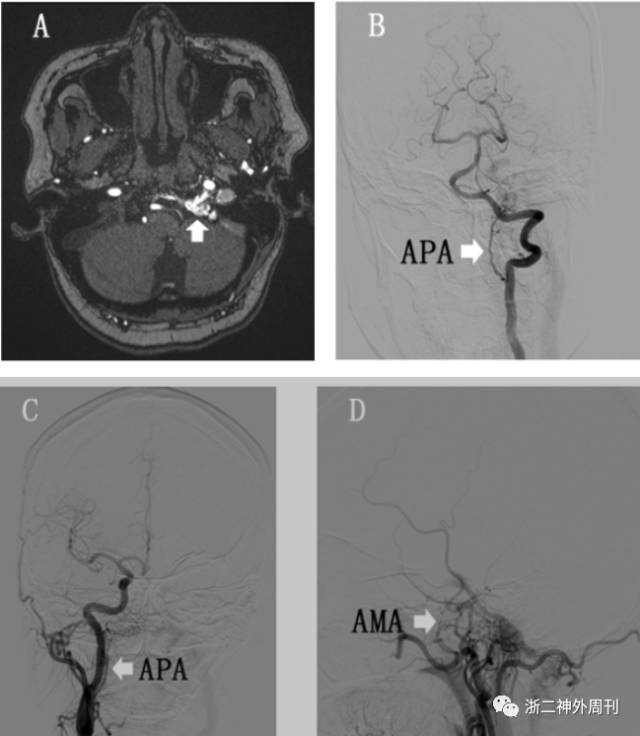

患者于5月前无明显诱因出现左侧耳鸣伴有左侧头痛,无听力下降等,未就诊。1月前症状有所加重,并出现左眼球结膜充血肿胀伴视物模糊,来我院就诊,MRA(3D-TOF )(图1A)检查提示左侧舌下神经管区异常血管。拟诊“硬脑膜动静脉瘘可能”收住入院。

入院后进一步 DSA检查,确诊为舌下神经管区硬脑膜动静脉瘘(hypoglossal canal dural arteriovenous fistulas,HC- DAVF),供血动脉主要为左侧咽升动脉,另外右侧咽升动脉、左侧脑膜前动脉均参与供血。瘘口位于左侧舌下神经管处,静脉引流向上通过岩下窦向海绵窦引流并返流到眼静脉和皮层静脉,向下回流到颈内静脉,并可见有髓周静脉引流(图1B-D)。

图1. A:3D-TOF MRA影显示左侧舌下神经管处异常的紊乱血管(白箭头);B-D:DSA结果提示双侧咽升动脉(APA)及左侧脑膜前动脉(AMA)供血(白色箭头)。